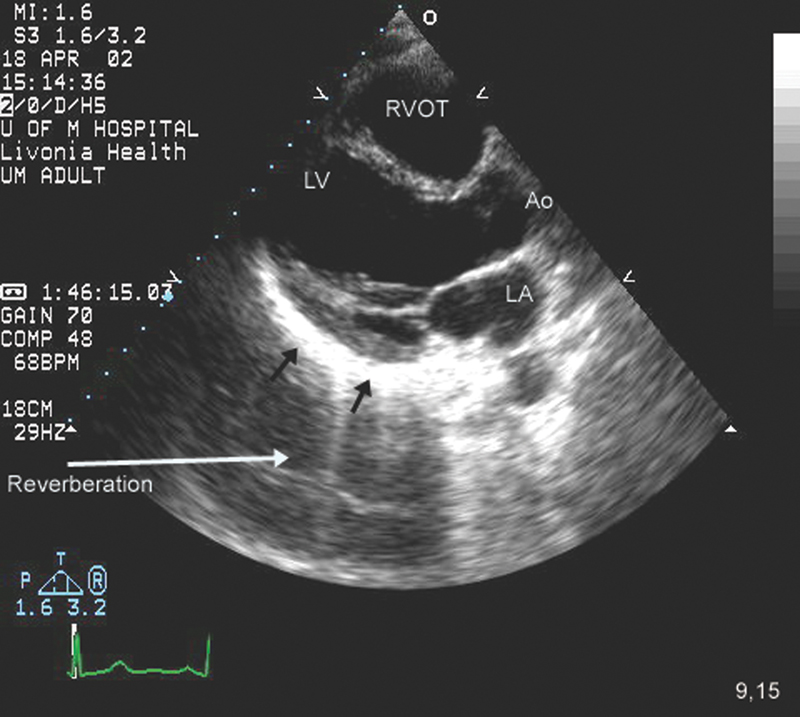

فحوصات تشخيصية لبعض امراض القلب والشرايين التاجية